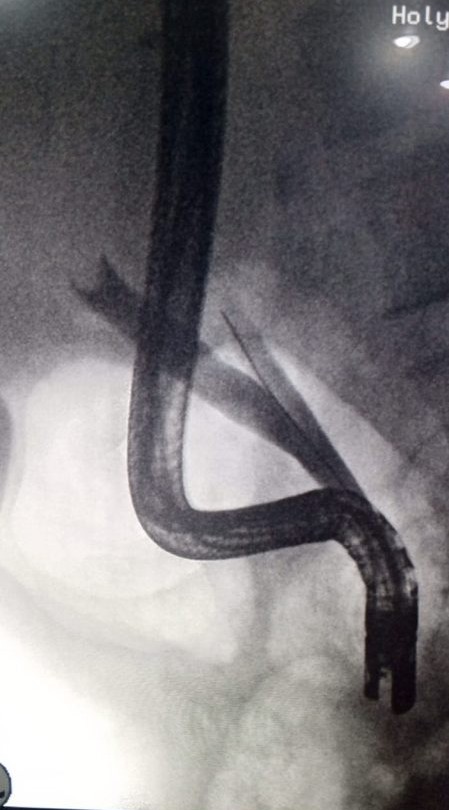

ERCP - Department of Gastroenterology, HFH

Obstructive jaundice and abdominal pain